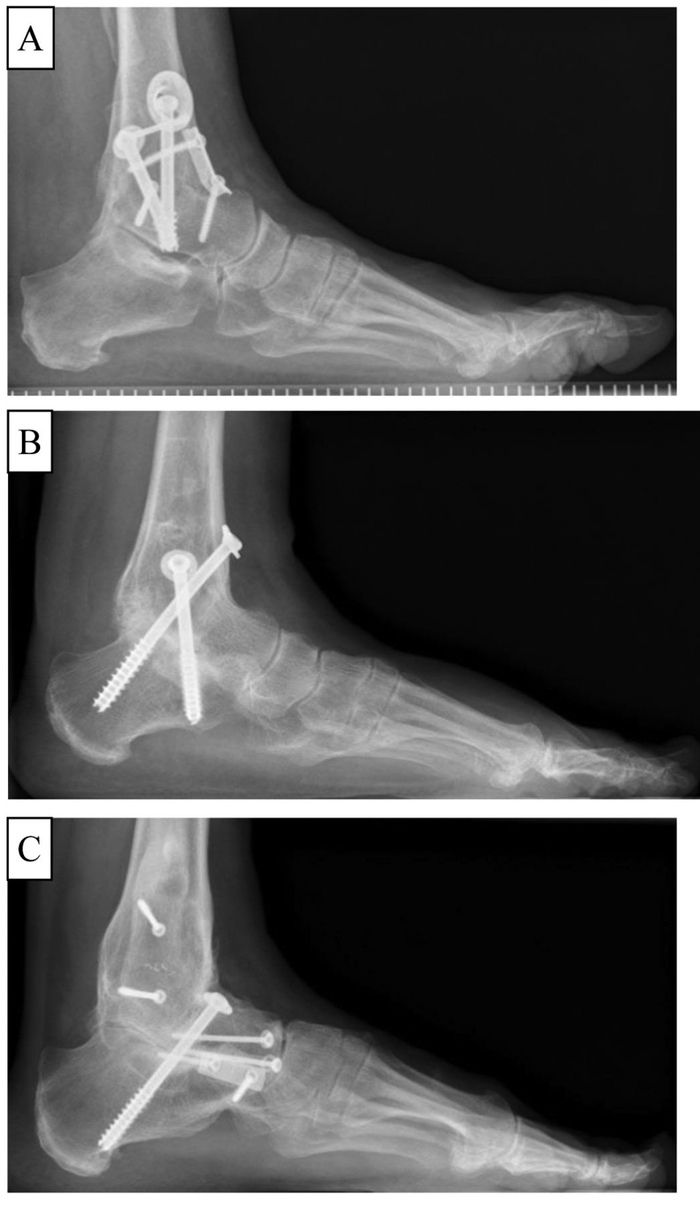

Кроме того, многие вирусы, хотя и предпочитают какой-то конкретный тип клеток, на деле заражают и множество других. Например, многие слышали, что ВИЧ поражает клетки иммунной системы, в первую очередь Т-лимфоциты. Однако, помимо них, ВИЧ создаёт вирусный резервуары в множестве других клетках и органах:

Места расположение резервуаров ВИЧ. Салатовым цветом - неповреждённая ДНК, серым - дефектная